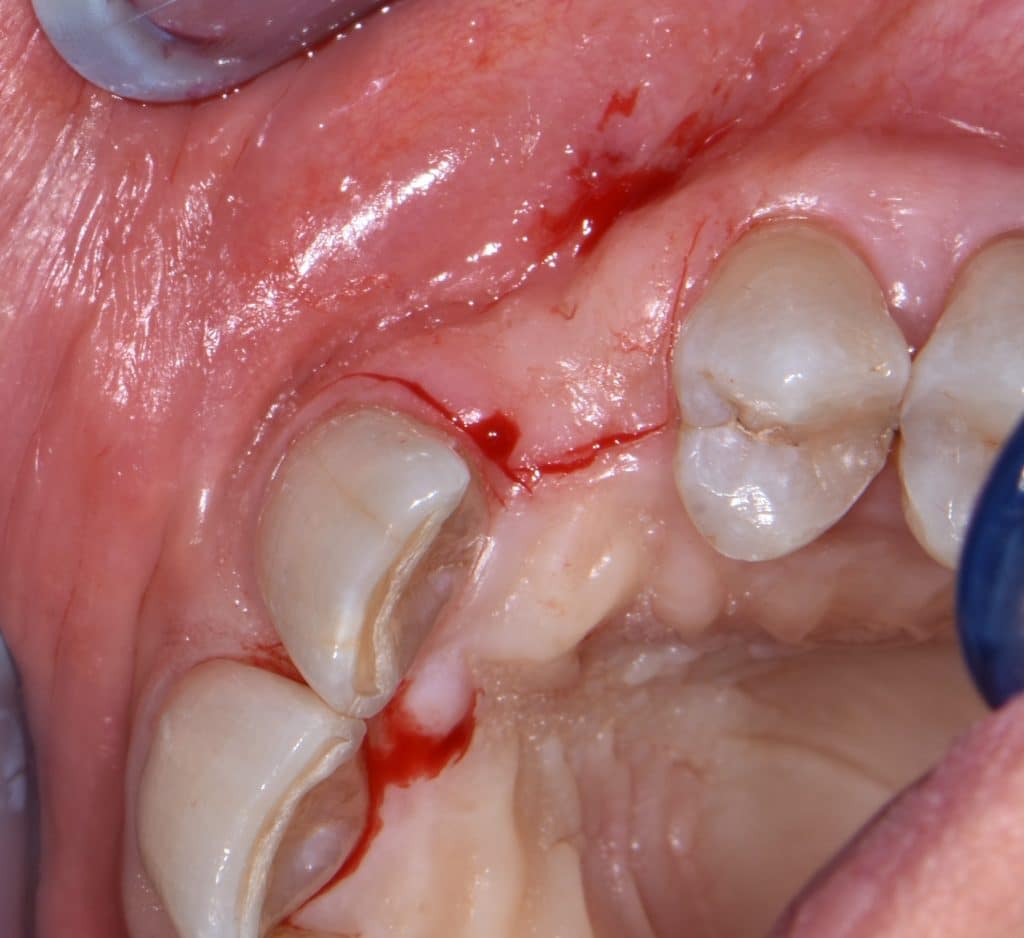

La pz N.G. di anni 52 (ASA 1) viene visitata nel mese di settembre 2017 per la mobilità ed inestetismo dell’elemento protesico 22, (foto iniziali sequenza 1) si evidenzia una frattura parziale della radice, si decide per l’estrazione ( foto sequenza 2) e sostituzione dell’elemento con un restauro implanto-protesico. Purtroppo la scarsa quota ossea apicale all’alveolo post-estrattivo (foto 2 rx) e l’alta valenza estetica dell’elemento ci rende cauti e si programma una socket preservation post estrattiva con l’ausilio delle membrane di prf (foto prf e socket sequenza 3 e 4). Durente i 5 mesi di guarigione la pz porta una protesi parziale mobile (foto 5,2) , a guarigione del sito post estrattivo si evidenzia una buona conservazione dei volumi osseo-gengivali,(foto guarigione sequenza 6) se pur presente una recessione distale all’elemnto 21.Nel mese di febbraio 2018 si procede all’inserimento di un impianto max-stability 3,75x12mm disegnando un lembo anticipato palatino per consentire un aumento dei tessuti vestibolari suturando con tecnica rool flap e trasformando l’elemento parziale mobile in una corona singola a carico immediato sul moncone temporameo applicando i concetti protesici bopt , (foto impianto moncone protesi provvisoria sequenza foto 7-8-9). Durante il periodo di maturazione dei tessuti molli vengono apportate opportune modifiche ai profili del provvisorio al fine di dare maggior spazio al tessuto gengivale, ( fotosequenza 10).Dopo circa 2 mesi dal protesizzazione provvisoria si è proceduto alla realizzazione del manufatto protesico con tecnica chair side sirona con l’ausilio del t-base (foto sequenza 11-12-13), realizzando in una sola seduta una corona in disilicato, ottenendo un risultato più che soddisfacente (Foto 14). Nel controllo a 3 mesi dal carico definitivo si apprezza la perfetta conservazione dei livelli ossei e gengivali. (foto sequenza 15).concludo con un follow up a 18 . Tengo a sottolineare che un caso come questo è stato conducibile con buoni risultati solo grazie alla piena fiducia della pz e alla sua massima motivazione e collaborazione. Ad oggi la pz sorride soddisfatta del risultato. E questo rappresenta la massima ricompensa di chi dedica tutto se stesso alla professione.